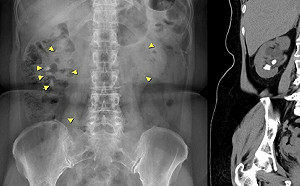

揪出反覆尿道結石「隱形殺手」!專業醫曝:與副甲狀腺亢進有關